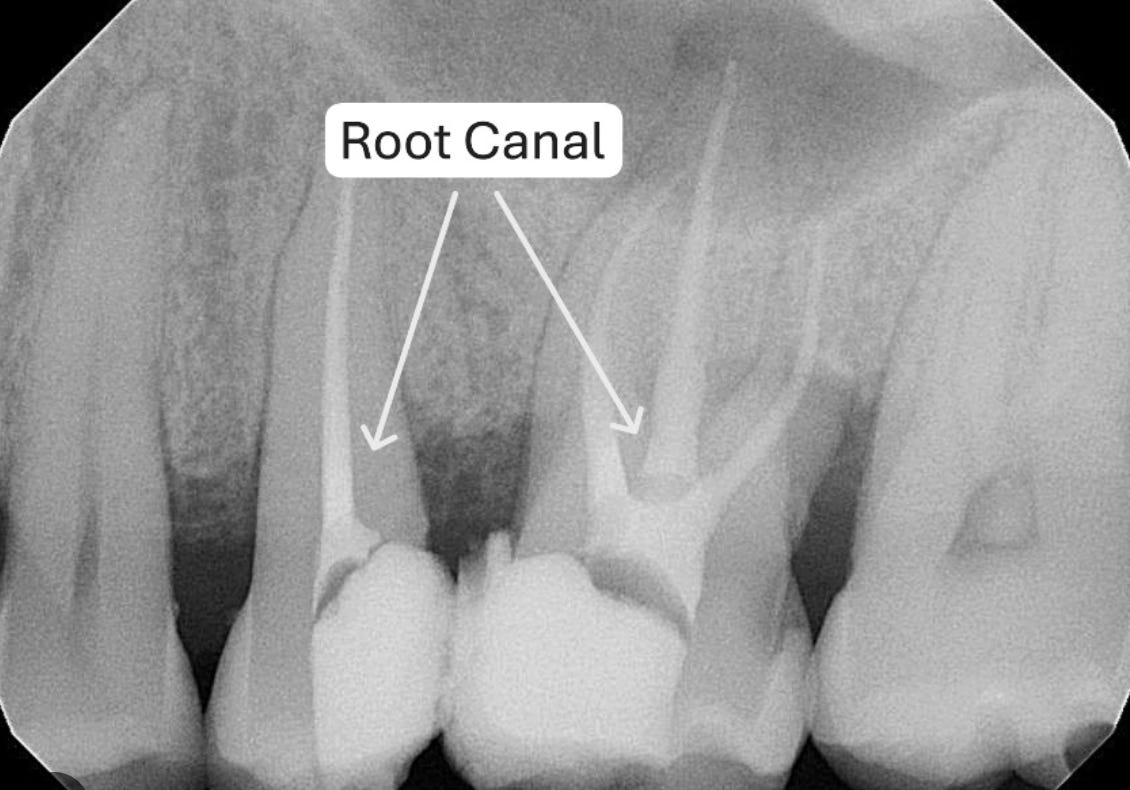

Root Canals: Sealed Infection, Systemic Consequences

Root canals are often presented as a routine solution—remove the nerve, seal the tooth, problem solved. But according to Dr. Thomas Levy, this approach ignores a critical biological reality: a dead tooth is still a tooth embedded in living bone, and once the blood supply is removed, the body has no way to deliver immune cells or oxygen to that tissue. The result is a sealed, anaerobic environment where pathogenic bacteria can thrive undetected. Levy explains that root-canaled teeth frequently harbor toxic microbial byproducts, including highly inflammatory sulfur compounds, which can leak into surrounding tissues and the bloodstream over time. These chronic, low-grade infections may remain asymptomatic locally while contributing to systemic inflammation, autoimmune activation, neurological symptoms, and cardiovascular stress. In this framework, root canals don’t eliminate infections—they encapsulate them, creating a persistent source of oxidative and immune burden that the body must continually manage.4 The only real solution to remove the source of infection is to remove the tooth.